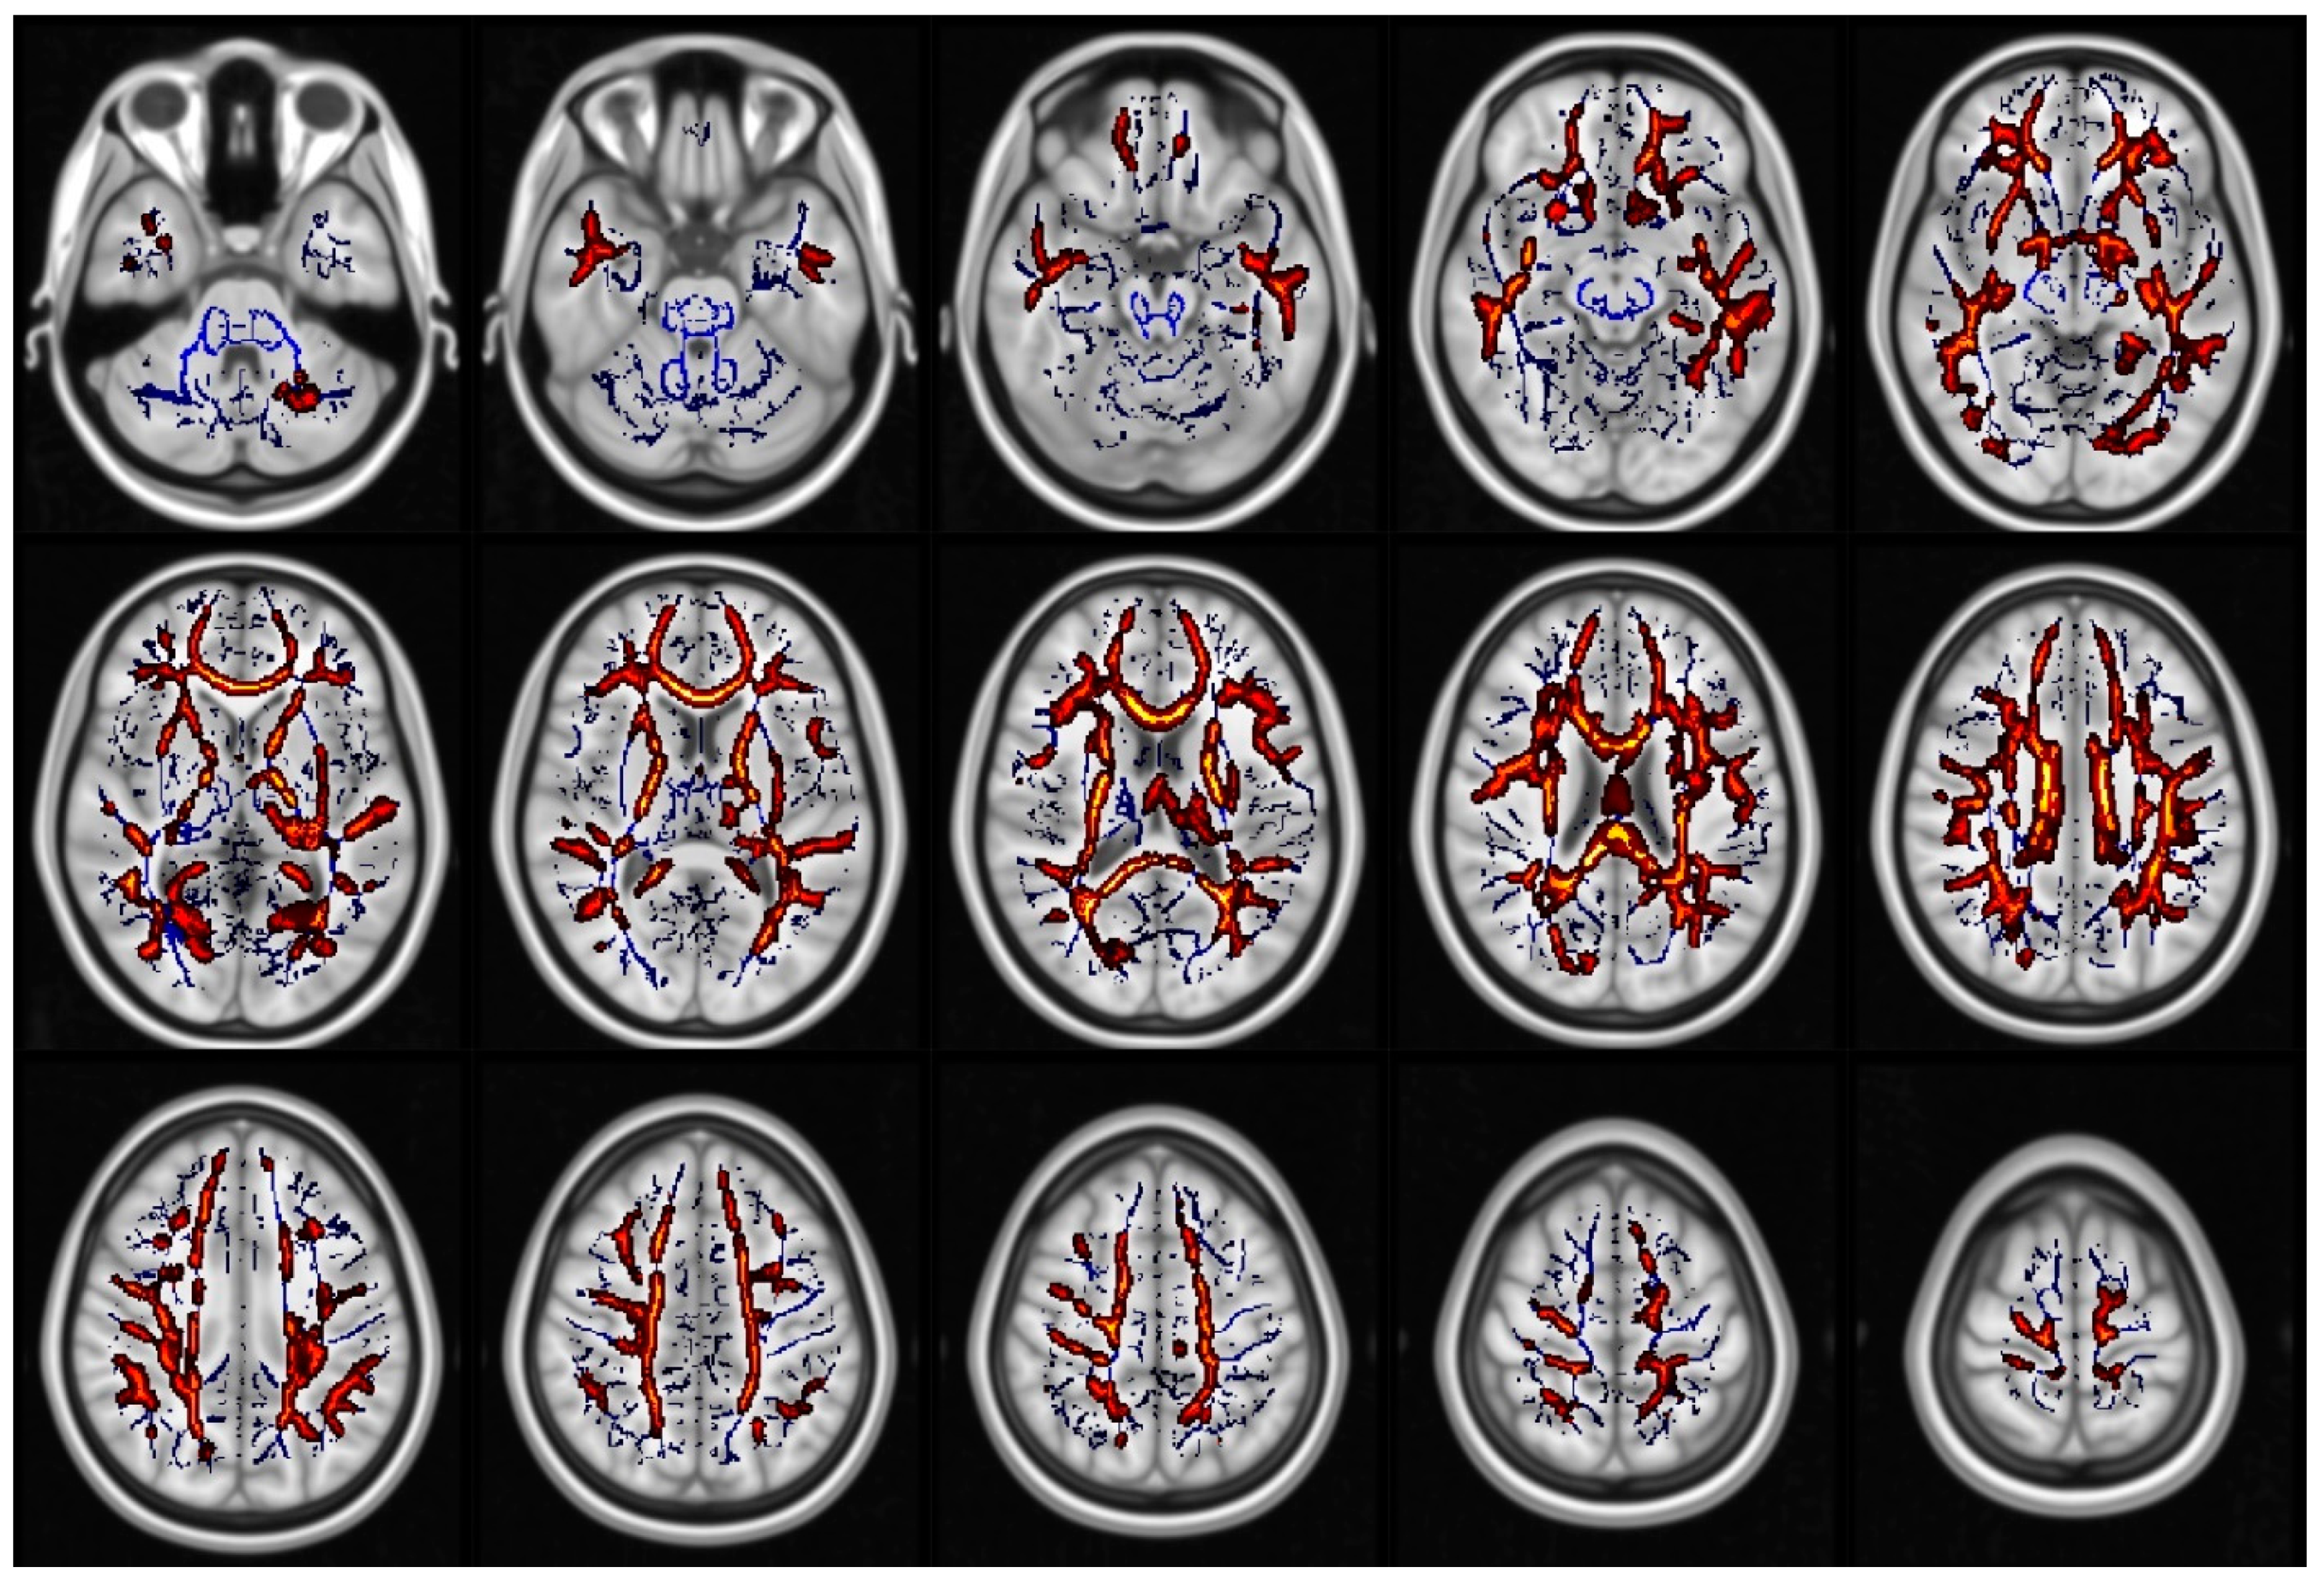

- Smith, S.M.; Jenkinson, M.; Johansen-Berg, H.; Rueckert, D.; Nichols, T.E.; Mackay, C.; E Watkins, K.; Ciccarelli, O.; Cader, M.Z.; Matthews, P.M.; et al. Tract-based spatial statistics: Voxelwise analysis of multi-subject diffusion data. NeuroImage 2006, 31, 1487–1505. [Google Scholar] [CrossRef] [PubMed]

- Smith, S.M.; Nichols, T.E. Threshold-free cluster enhancement: Addressing problems of smoothing, threshold dependence and localisation in cluster inference. NeuroImage 2009, 44, 83–98. [Google Scholar] [CrossRef] [PubMed]